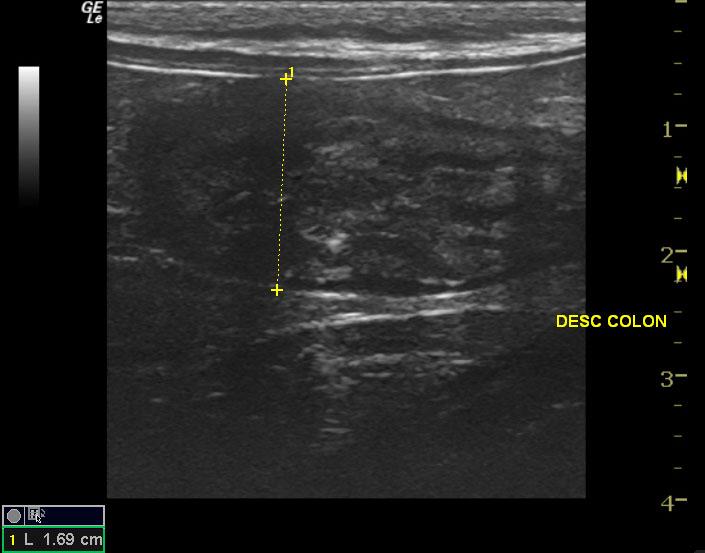

A 1-year-old male neutered Ragdoll cat was with history of chronic eye problems presented for decreased appetite and loose stools for 3 days. Physical exam found patient pyrexic at 104.4 degrees fahrenheit. Suspected enlarged lymph nodes were found on abdominal palpation. Subcutaneous fluids were administered, and patient was discharged with appetite stimulants. Blood chemistry and CBC were within normal limits. FELV/FIV and FIP tests were all negative. Toxoplasma results were normal.